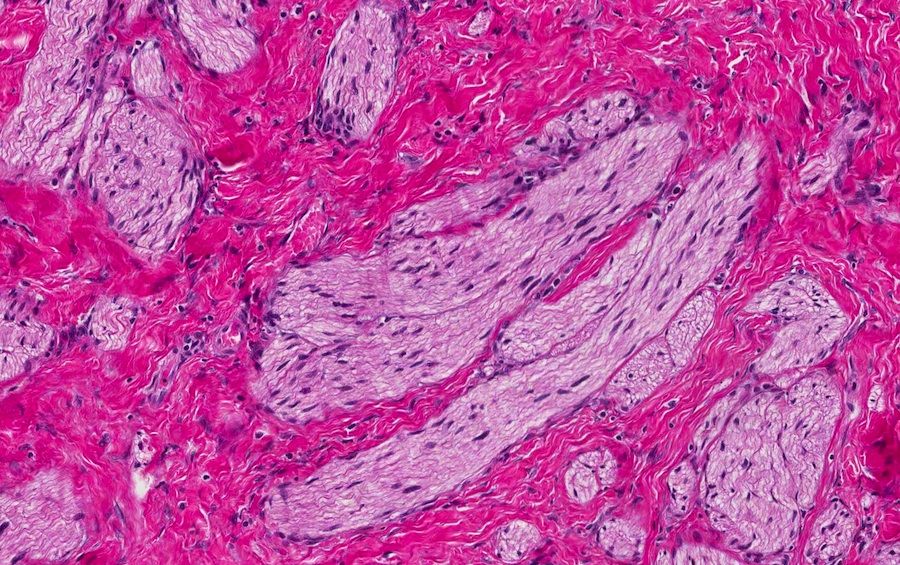

Microscopic images:

Both cases showed disorganized and thickened nerve bundles composed of spindle shaped cells, without atypia. Case A also showed a focal foreign body type giant cell reaction adjacent to the disorganized nerve bundles and a strongly immunoreactive S100 stain.

Histology typically shows hyperplastic nerve bundles, positive for S100.

Microscopic images:

Both cases showed disorganized and thickened nerve bundles composed of spindle shaped cells, without atypia. Case A also showed a focal foreign body type giant cell reaction adjacent to the disorganized nerve bundles and a strongly immunoreactive S100 stain.

Histology typically shows hyperplastic nerve bundles, positive for S100.